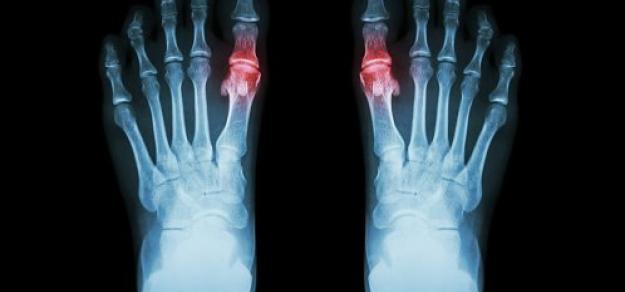

Alopurinol versus atención habitual en pacientes del Reino Unido con cardiopatía isquémica (ALL-HEART)